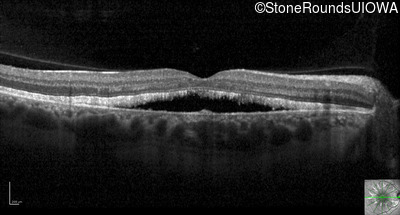

Optical Coherence Tomography - Right - 20/20

Exemplar / OCT Stack

OCT Stack